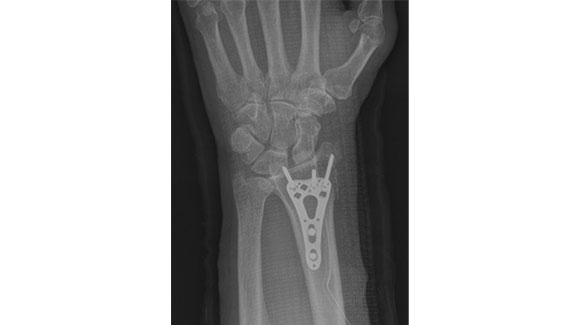

骨折手術(前腕)

前腕の骨折手術で多いのは、橈骨遠位端骨折といって手首の骨折です。腕時計ぐらいの部位で骨折し、握力や手の機能が落ちてしまうため、骨折部分の離れ具合により手術を必要とする例が多いです。

手術では全身麻酔または上半身のみのブロック手術で行う事が多いです。

手の掌側(てのひら側)の腕時計の高さ近くで縦に切開を行い、筋肉をよけて骨折部分を正しく整復します。その後に上記のような金属性のプレートを用いて固定を行います。手術は1時間弱で終わり、翌日に退院する事が多いです。